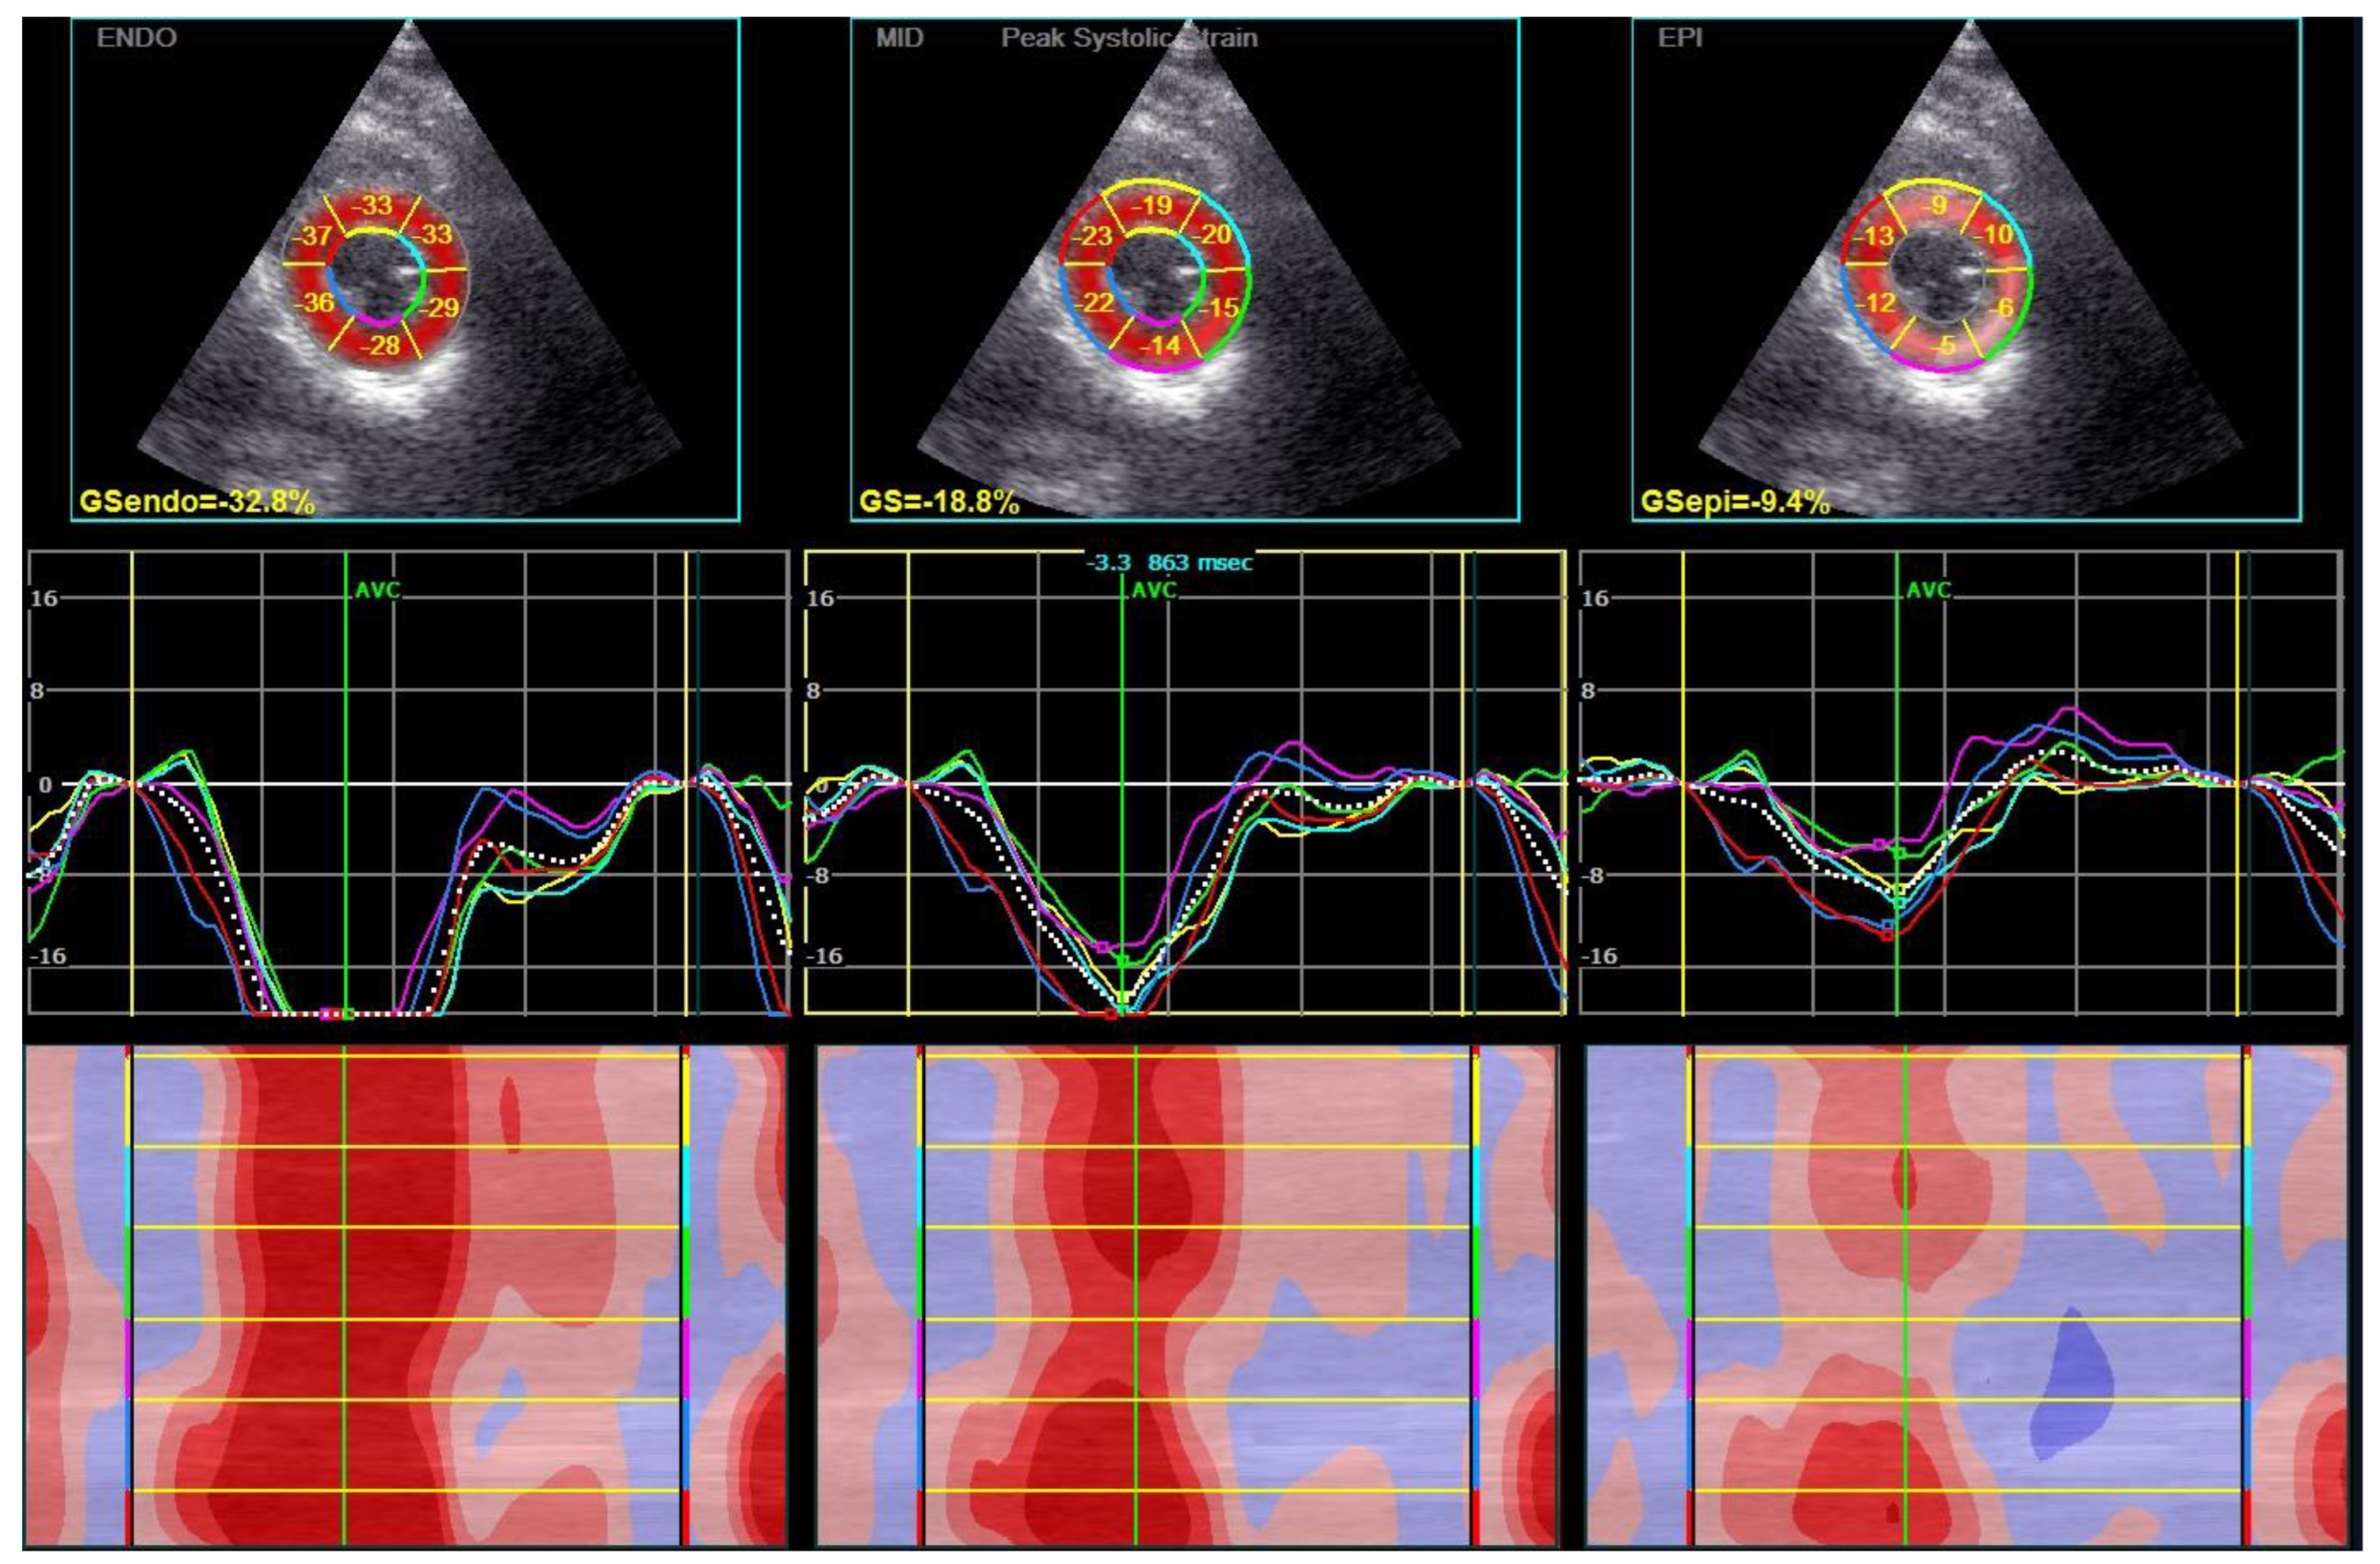

2.4. Two-Dimensional Speckle-Tracking Echocardiography

- Nagata, Y.; Wu, V.C.; Otsuji, Y.; Takeuchi, M. Normal range of myocardial layer-specific strain using two-dimensional speckle tracking echocardiography. PLoS ONE 2017, 12, e0180584. [Google Scholar] [CrossRef]

| GLS, % | apical 4 chamber | −18.6 (−21.6, −16.5) | −19.5 (−21.6, −17.2) | −17.7 (−20.9, −15.6) | 0.189 |

| apical 2 chamber | −19.4 (−22.5, −15.6) | −20.6 (−23.3, −16.9) | −18.4 (−19.6, −15.6) | 0.060 | |

| apical 3 chamber | −19.6 (−21.7, −14.1) | −19.9 (−21.5, −15.6) | −18.6 (−21.8, −13.2) | 0.373 | |

| average | −19.1 (−21.6, −16.1) | −19.9 (−22.0, −16.3) | −18.2 (−19.6, −16.1) | 0.115 | |

| GCS, % | epicardial | −9.2 (−11.7, −9.2) | −8.8 (−11.2, −6.8) | −10.2 (−12.1, −7.6) | 0.348 |

| mid-wall | −14.9 (−17.2, −11.1) | −15.1 (−17.1, −11.1) | −14.9 (−17.2, −11.8) | 0.824 | |

| endocardial | −24.8 (−29.0, −18.5) | −24.3 (−29.7, −18.8) | −25.3 (−27.6, −18.4) | 1.000 | |

| average | −16.4 (−18.8, −11.8) | −16.2 (−18.9, −11.8) | −16.4 (−18.4, −13.5) | 0.962 | |